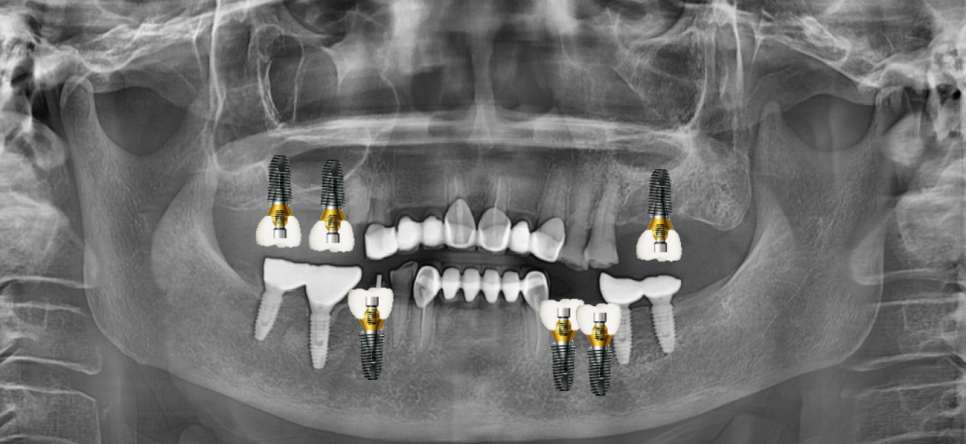

임플란트 위아래 합하여 6개

식립이 필요하다

명일동 치과에서 상담을 진행해드렸습니다.

윗니 어금니의 경우

코 막을 들어올리는 상악동 거상술이 필요했기 때문입니다.

그래서 임플란트 치료 기간도 위턱기준 4-6개월

아래턱 기준 2-3개월 소요되는데요.

아래에 비해 2배 이상 걸리는 이유가

타고 나기를 약한 뼈라

뼈와 임플란트가 고정되기까지

시간이 걸리는 편입니다.